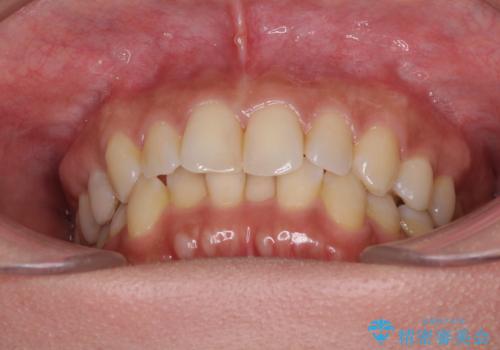

マウスピース矯正の注意事項(リスク・副作用など)

- 口腔内・歯並びの状態によっては対応できない場合があります

- マウスピース型矯正装置の長時間装着(1日20時間以上)が必須です

- 治療計画通りに進めるためには、患者様の意志が重要になります

- 矯正治療後の保定が不十分だと後戻り(元の位置に戻ろうとする動き)をします

- 薬機法対象外の矯正歯科装置のため医薬品副作用被害救済制度の対象外となる場合があります

- 自費診療(保険適用外)となります